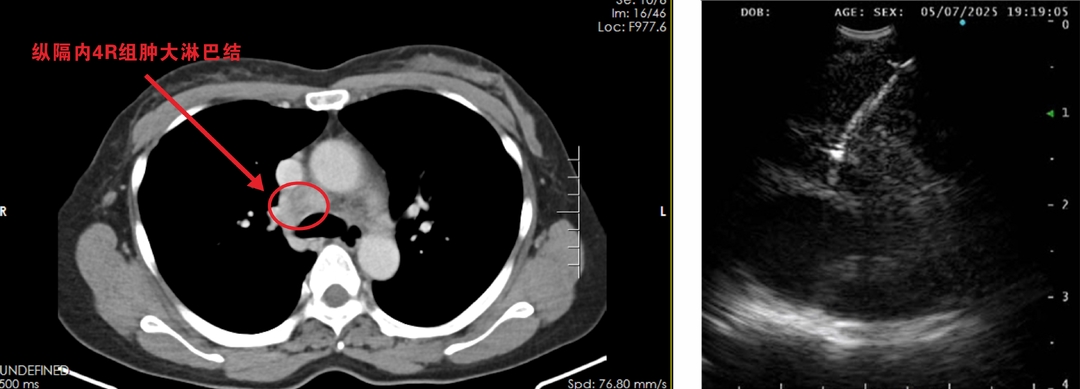

胸部CT检查显示,陈女士右肺上叶存在占位性病变、右肺门及纵隔多发淋巴结肿大,考虑恶性肿瘤伴淋巴结转移。

左图为CT所示病灶部位;右图为EBUS-TBNA超声影像。

“患者病灶位置特殊,紧贴肺动脉主要分支,传统活检方式风险较高。”呼吸与危重症医学科二区主任陈茂辉介绍,科室讨论后决定采用EBUS-TBNA术,该技术能实现实时超声引导下的精准穿刺,有效规避血管风险。

“EBUS-TBNA技术通过将超声探头与支气管镜相结合,能够清晰显示纵隔、肺门等深部组织的实时影像,实现精准活检取样。”陈茂辉介绍,相比传统开胸手术或纵隔镜检查,该技术仅需2-3毫米的微创切口,就能安全获取病变组织,避免了出血、气胸等并发症风险,具有微创、精准、安全、费用低等优点。